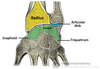

The typical rib consists of a head, neck and body:

The head is wedge shaped, and has two articular facets separated by a wedge of bone. One facet articulates with the numerically corresponding vertebrae, and the other articulates with the vertebrae above.

The neck contains no bony prominences, but simply connects the head with the body. Where the neck meets the body there is a roughed tubercle, with a facet for articulation with the transverse process of the corresponding vertebrae.

The body, or shaft of the rib is flat and curved. The internal surface of the shaft has a groove for the neurovascular supply of the thorax, protecting the vessels and nerves from damage.